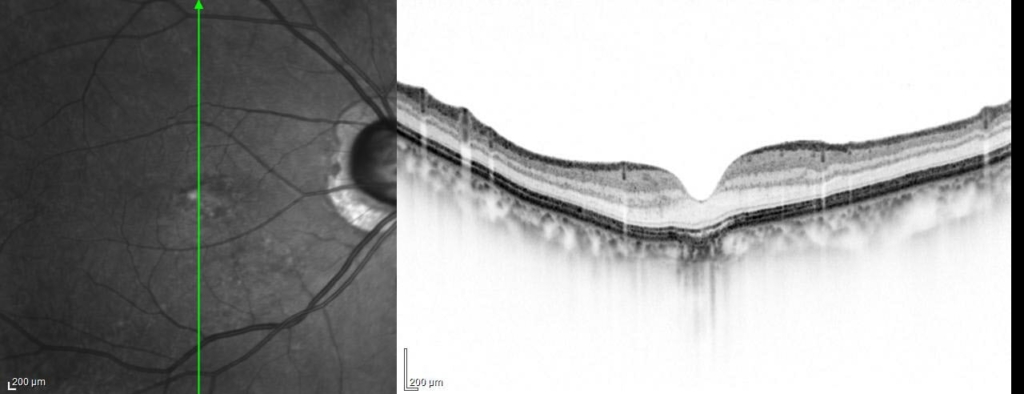

2018/10

中心窩の網膜色素上皮(RPE)と脈絡膜がU字の陥凹がみられる。